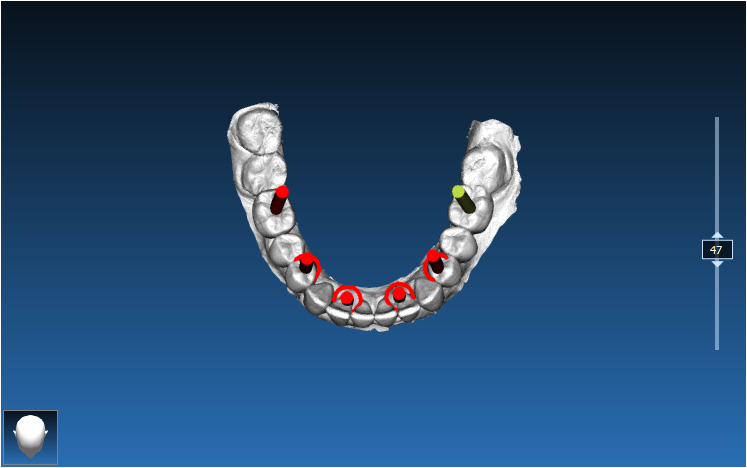

Dual Arch Rehabilitation — All-on-4 & All-on-6

Complete upper and lower jaw rehabilitation. All-on-4 concept for maxilla and All-on-6 for mandible with custom surgical guides.